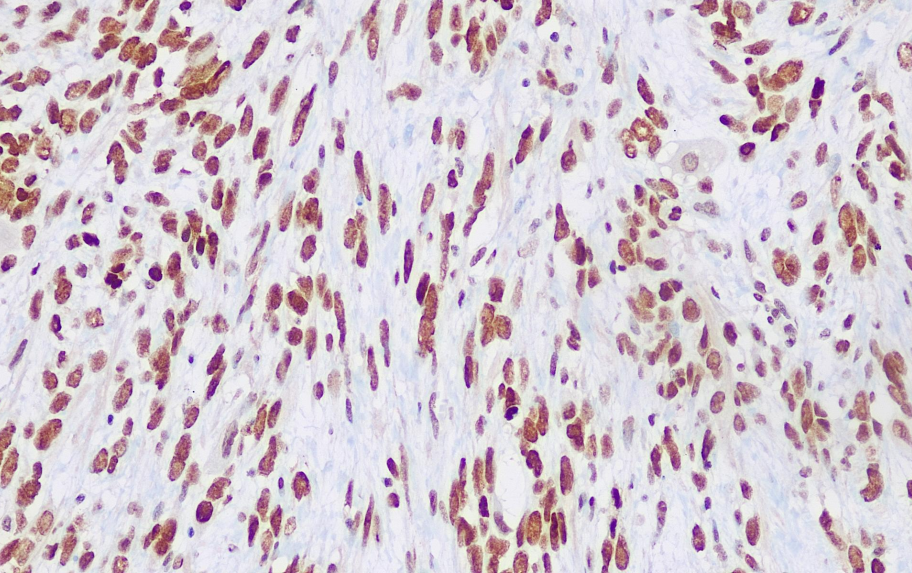

Cellular localization: nucleus

Positive control: Rhabdomyosarcoma

The INI-1 gene is the encoding gene of a protein component of unknown function in the hSWI/SNF chromatin remodeling complex, and mutations or deletions often occur in malignant rhabdoid tumors (MRT). The overall survival rate of MRT is relatively low compared to its suspected diseases (medulloblastoma and sPNETs). The characteristic of MRT is the lack of INI-1 nuclear markers. Most medulloblastomas and sPNETs are based on INI-1 as a reference, and thus can be used in the research of such diseases.

The INI-1 antibody reagent can specifically bind to the INI-1 molecular antigen. The immunohistochemical kit containing the INI-1 antibody reagent is suitable for the precise diagnosis of malignant rhabdoid tumor and epithelioid sarcoma.